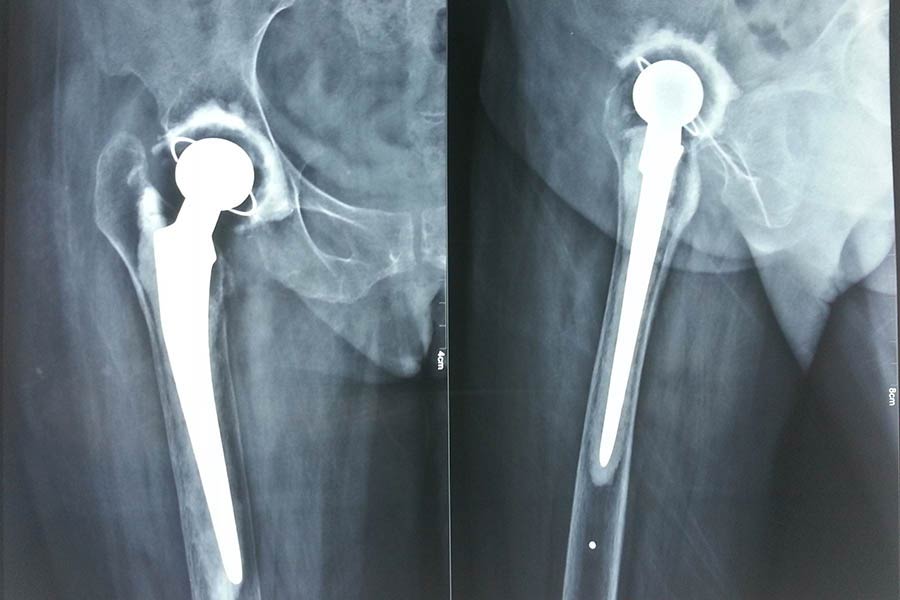

Total Hip Replacement

Case 1